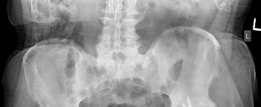

Preoperative Radiological Assessment/Imaging

(Figs. 19.22, 19.23, and 19.24)

Diagnosis : Dislocated left total hip arthroplasty secondary to septic loosening and suspected corrosion and trunnionosis of the femoral stem (Figs. 19.23 and 19.24).